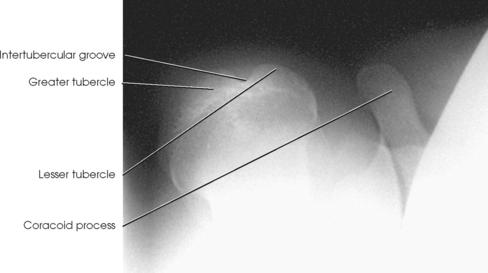

The lesser tubercle is situated on the anterior surface of the bone, immediately below the anatomic neck (Figs. 5-6 and 5-7; see Fig. 5-5). The tendon of the subscapular muscle inserts at the lesser tubercle. The greater tubercle is located on the lateral surface of the bone, just below the anatomic neck, and is separated from the lesser tubercle by a deep depression called the intertubercular (bicipital) groove. The superior surface of the greater tubercle slopes posteriorly at an angle of approximately 25 degrees and has three flattened impressions for muscle insertions. The anterior impression is the highest of the three and affords attachment to the tendon of the supraspinatus muscle. The middle impression is the point of insertion of the infraspinatus muscle. The tendon of the upper fibers of the teres minor muscle inserts at the posterior impression (the lower fibers insert into the body of the bone immediately below this point).

Fig. 5-7 Superior aspect of humerus. Horizontal section through scapulohumeral joint showing normal anatomic relationships.